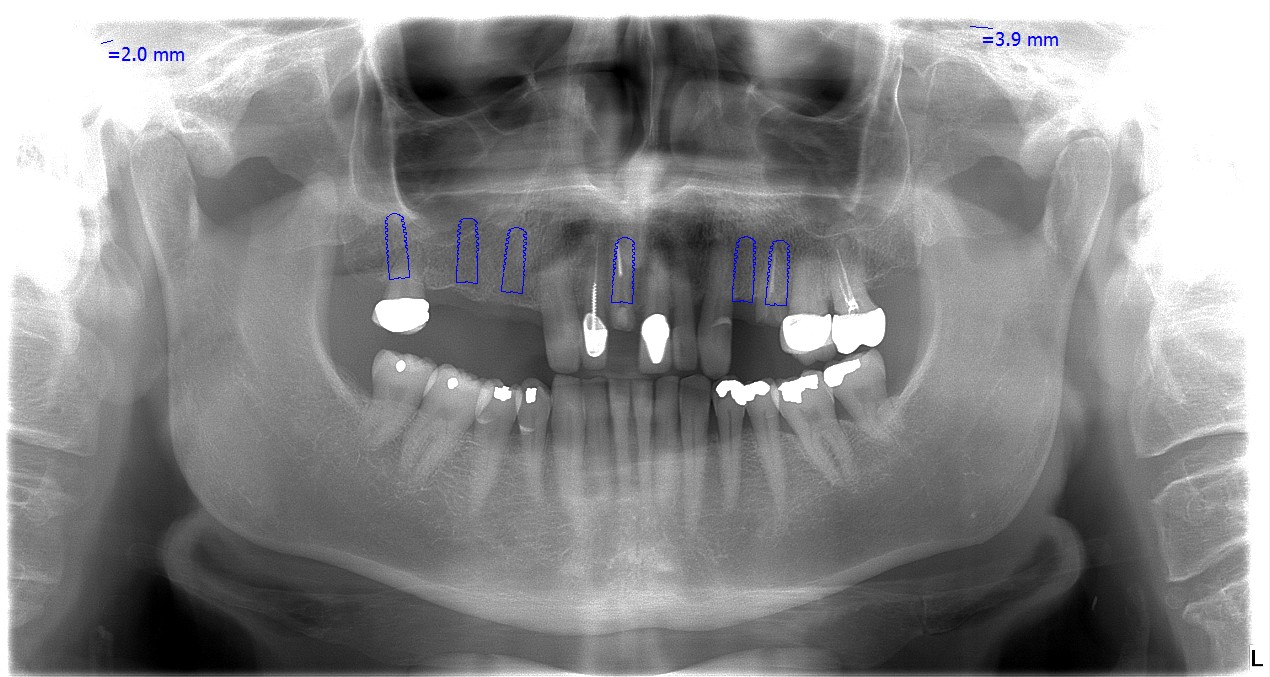

After his initial dental consultation done on the day of his 1st visit to us, our implantologist Dr. Marek prepared a personalized treatment plan for John, which included a 12 unit ceramic bridge fitted on 5 dental implants.